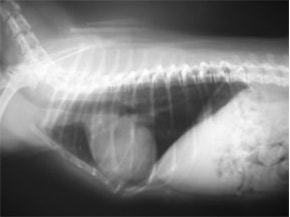

D:胸部レントゲン写真 正面像

E:胸部レントゲン写真 側面像

左側胸壁心尖部領域を最強点とするLevine 5/6の収縮期性心雑音が聴取された。

胸部レントゲン検査において重度の心拡大と肺水腫が認められた。超音波検査では、重度の僧帽弁閉鎖不全症、三尖弁閉鎖不全症、中程度の大動脈弁閉鎖不全症を合併していることが判明した。三尖弁逆流速度から肺高血圧症が示唆された。

ACE阻害薬、ピモベンダン、硝酸イソソルビド徐放剤、ベラプロストナトリウム、利尿剤としてフロセミドとスピロノラクトンを用いて治療を行った。